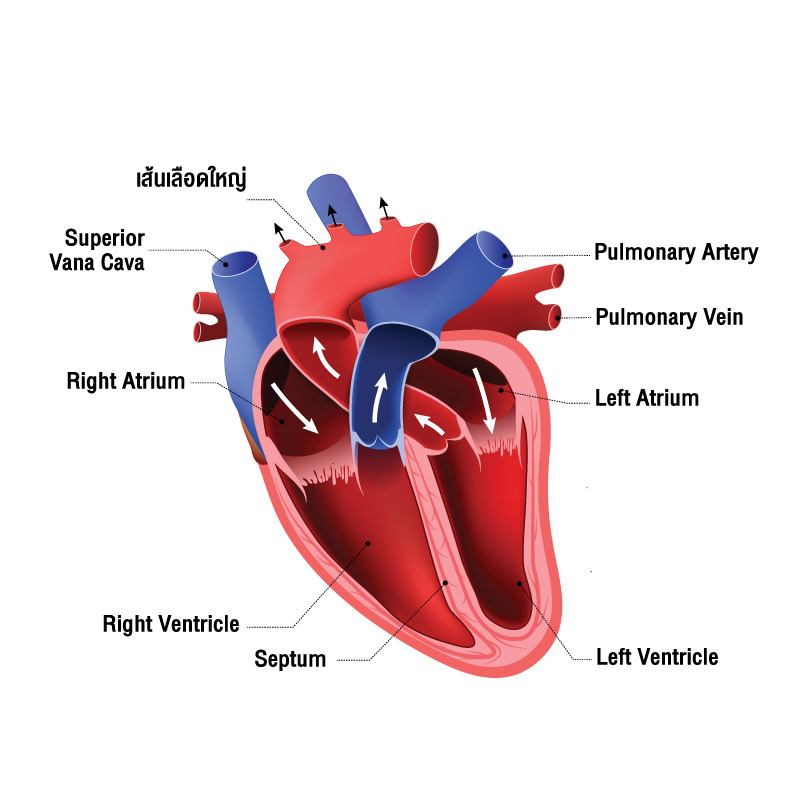

ระบบไหลเวียนโลหิต ทำหน้าที่อะไร และมีส่วนประกอบสำคัญอะไรบ้าง

37,900+ การไหลเวียนของเลือด ภาพถ่ายสต็อก รูปภาพ และภาพปลอดค่าลิขสิทธิ์ … หัวใจกับการไหลเวียนของเลือด – ระบบไหลเวียนโลหิต

หัวใจกับการไหลเวียนของเลือด – ระบบไหลเวียนโลหิต ม.2 ระบบหมุนเวียนเลือด | Science – Quizizz

ม.2 ระบบหมุนเวียนเลือด | Science – Quizizz ระบบไหลเวียนเลือด: หัวใจ

การไหลเวียนของปอด ภาพประกอบสต็อก – ดาวน์โหลดรูปภาพตอนนี้ – ปอด – ระบบ … Heart Diagram กายวิภาคศาสตร์ร่างกายมนุษย์ระบบไหลเวียนโลหิตหัวใจ …

เข้าใจการทำงานของหัวใจ (Understanding how your Heart Functions) | HD … 280+ Carotid Artery ภาพประกอบ กราฟิกแบบเวกเตอร์ปลอดค่าลิขสิทธิ์ และคลิป …